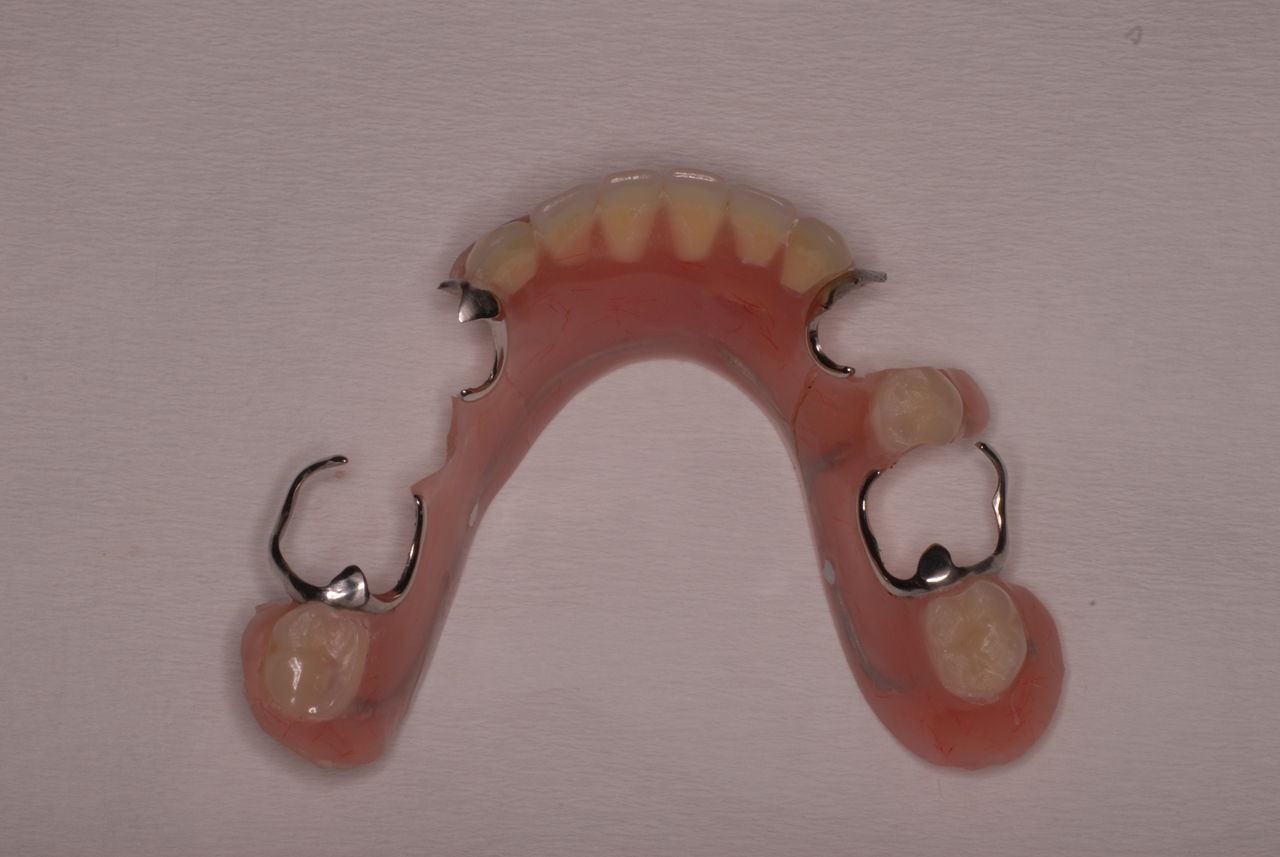

クラスプという歯を取り囲むワイヤ−が折れたりしてまともに機能していません。構造的な問題もあるのでしょうがヒビも目立ちます。殆ど使わずに御蔵入りとなったようです。値段の問題からかそうではないか判然としませんが、入れ歯というのは残りの歯や歯周病の治療がある程度完了してからでないと良い機能的な入れ歯などはできません。せいぜい治療中用の簡素な物を作成して歯や歯茎の病気が治るのを待ちながら様子をみるしかないのです。